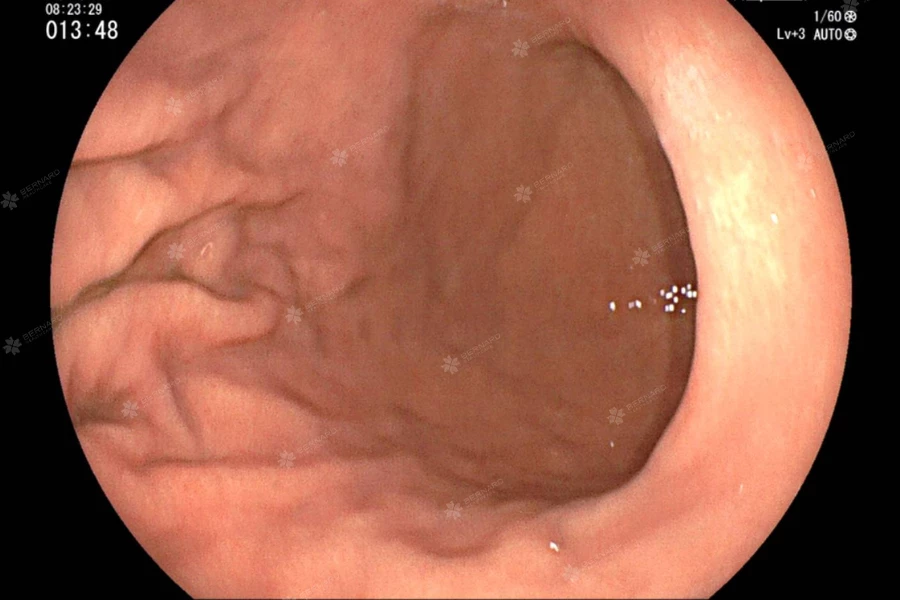

Tại Nhật Bản, tỷ lệ phát hiện tổn thương tiền ung thư ở đại tràng luôn duy trì ở mức cao, nhờ vào yếu tố cốt lõi là bác sĩ được yêu cầu phải soi kỹ và quan sát đủ toàn bộ đại tràng với thời gian rút ống sớm nhất là phải bằng hoặc hơn 6 phút. Trong tình hình phổ biến ở Việt Nam, nội soi tiêu hoá thường bị xem nhẹ, thậm chí chỉ là một thủ thuật đơn giản cần nhanh, gọn và sớm có kết quả. Tuy nhiên khi hợp tác chuyên sâu với Nhật Bản, Bernard Healthcare dưới sự đồng hành của chuyên gia nội soi hàng đầu cam kết bảo đảm mỗi ca nội soi là một quy trình chuẩn mực, chính xác đến từng phút, từng khung hình.

Thời gian qua, tuân thủ chuẩn Nhật Bản, Bernard đã nghiêm túc đảm bảo nguyên tắc soi kỹ, soi đủ và soi không bỏ sót. Điều đáng nói là trong mỗi ca soi, bác sĩ không chỉ cố gắng hoàn thành thủ thuật nhanh – mà dành thời gian gấp đôi trung bình thông thường nhằm đảm bảo quan sát kỹ từng vị trí dễ bị bỏ sót: các góc giải phẫu, đáy manh tràng, trực tràng thấp, …; Làm sạch hoàn toàn đại tràng trước khi đánh giá hình ảnh và sau cùng là ghi hình bằng video toàn bộ quá trình, lưu để xem lại hay nếu cần kiểm tra chéo.

Bác sĩ Kinoshita Koshi - chuyên gia nội soi cao cấp từ Bệnh viện Trung ương Kyoto Min-iren, cũng cho biết: “Ở Nhật, một ca nội soi dạ dày nếu nhanh hơn 6 phút là không đạt. Nhưng quan trọng hơn là bác sĩ cần biết vì sao mình phải soi kỹ như vậy – vì một tổn thương nhỏ bị bỏ sót có thể trở thành ung thư sau vài năm”.

Tất nhiên không chỉ giúp bác sĩ cải thiện kỹ năng, việc soi kỹ còn trực tiếp mang lại nhiều lợi ích cho người bệnh, như phát hiện sớm polyp hoặc tổn thương tiền ung thư; Giảm tỷ lệ bỏ sót, đặc biệt ở người từng nội soi trước đó nhưng chưa kỹ; Có lộ trình theo dõi cụ thể sau soi, tránh tâm lý “soi rồi là xong”…

Một bệnh nhân 48 tuổi sau ca nội soi sáng 23/7 cũng tâm sự: “Lần trước tôi nội soi đại tràng ở chỗ khác tổng cộng chỉ khoảng 10 phút, bác sĩ nói bình thường. Lần này tại Bernard soi kỹ hơn, còn cho tôi xem video đoạn niêm mạc hơi bất thường. Bác sĩ tư vấn rất rõ và nhẹ nhàng. Tôi cảm thấy yên tâm hơn rất nhiều”.